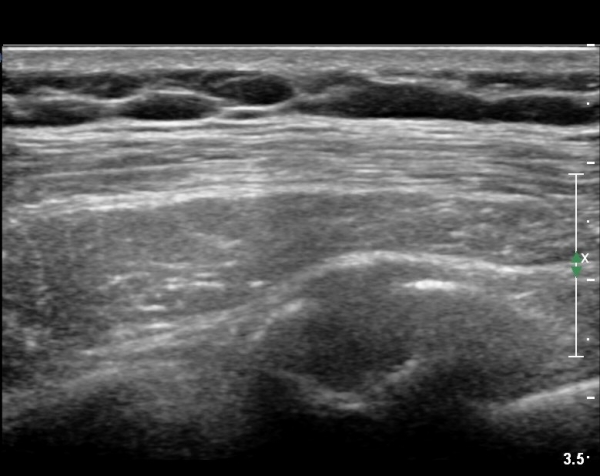

lin longitudinal scan of 7th. rib, appearance of bony mass(protrusion) just like callus(image 1).

on moving of prove a little, there is bony protrusion(osteoblastic lesion) and hypoechoic(osteolytic)  lesion(image 2, 3, 4).

As like this case, visualization of osteoblastic lesion and osteolytic lesion in simultaneously  suggests a malignant mass.